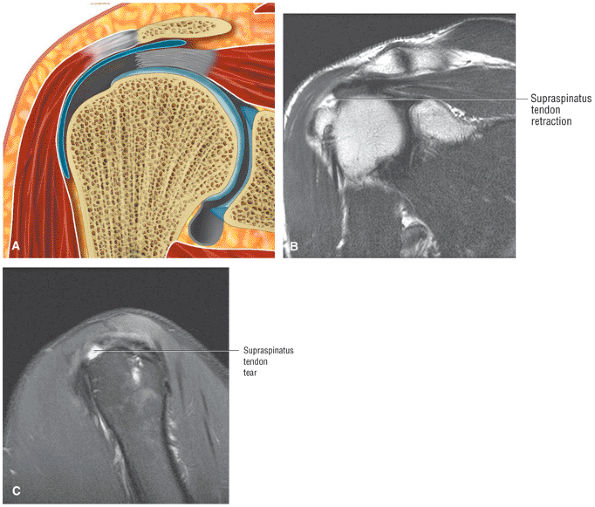

Rotator cuff tears should be measured in the coronal and sagittal planes.